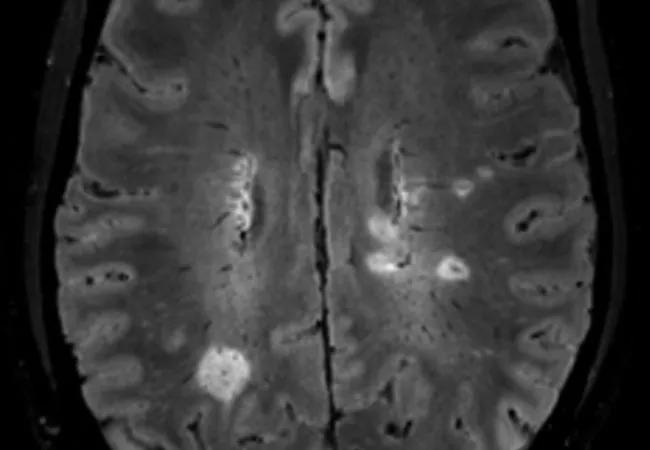

Detection of the central vein sign on brain imaging showed similar accuracy as oligoclonal bands in cerebrospinal fluid for the diagnosis of multiple sclerosis (MS) in a retrospective analysis of the Central Vein Sign in the Early Diagnosis of MS (CAVS-MS) pilot study.

The finding, reported in a poster presentation at the 38th Congress of the European Committee for Treatment and Research in Multiple Sclerosis (ECTRIMS 2022), is a notable boost for the potential utility of the central vein sign, a blood vessel seen within lesions in white matter on fluid-attenuated inversion recovery (FLAIR) MRI sequences.

“The diagnostic performance of the central vein sign detected by FLAIR* was similar to that of OCB in CSF,” says the study’s first author, Karlo Toljan, MD, a neurology resident at Cleveland Clinic. “Using the central vein sign as a diagnostic criterion may one day decrease the need for invasive CSF investigations and enable earlier and more accurate MS diagnosis.”

The central vein sign — best detected using FLAIR* (i.e., combining FLAIR with high-resolution contrast-enhanced T2*-weighted imaging for detection of central veins) — is increasingly recognized as a new biomarker that might improve diagnostic accuracy and may reduce the need for obtaining a CSF sample.

Image at top: Representative brain MRI with lesions showing the central vein sign.